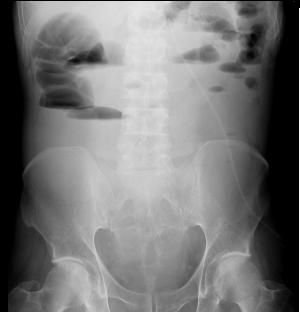

Image hydro-aerique du colon d'une

occlusion du colon . Aspect du colon en distendue

avec image des plies des haustrals de cette bord en

intercale avec des haustrals du bord oppose |